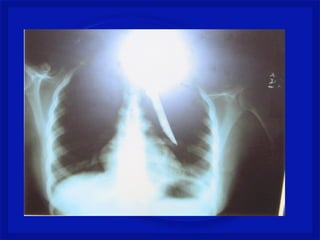

•Perfuração da coluna (arma branca, tiro

ou estilhaço de bomba na coluna)

•Lesão medular completa ou incompleta,

associada ou não a lesão dos nervos

espinhais e/ou tronco dos plexos

nervosos.

•Quadro neurológico é variável.

Mecanismo de Trauma Raqui-

Medular Penetrante

•Perfuração da coluna(arma branca, tiro ou estilhaço de bomba na coluna) •Lesão medular completa ou incompleta, associada ou não a lesão dos nervos espinhais e/ou tronco dos plexos nervosos. •Quadro neurológico é variável. Mecanismo de Trauma Raqui- Medular Penetrante